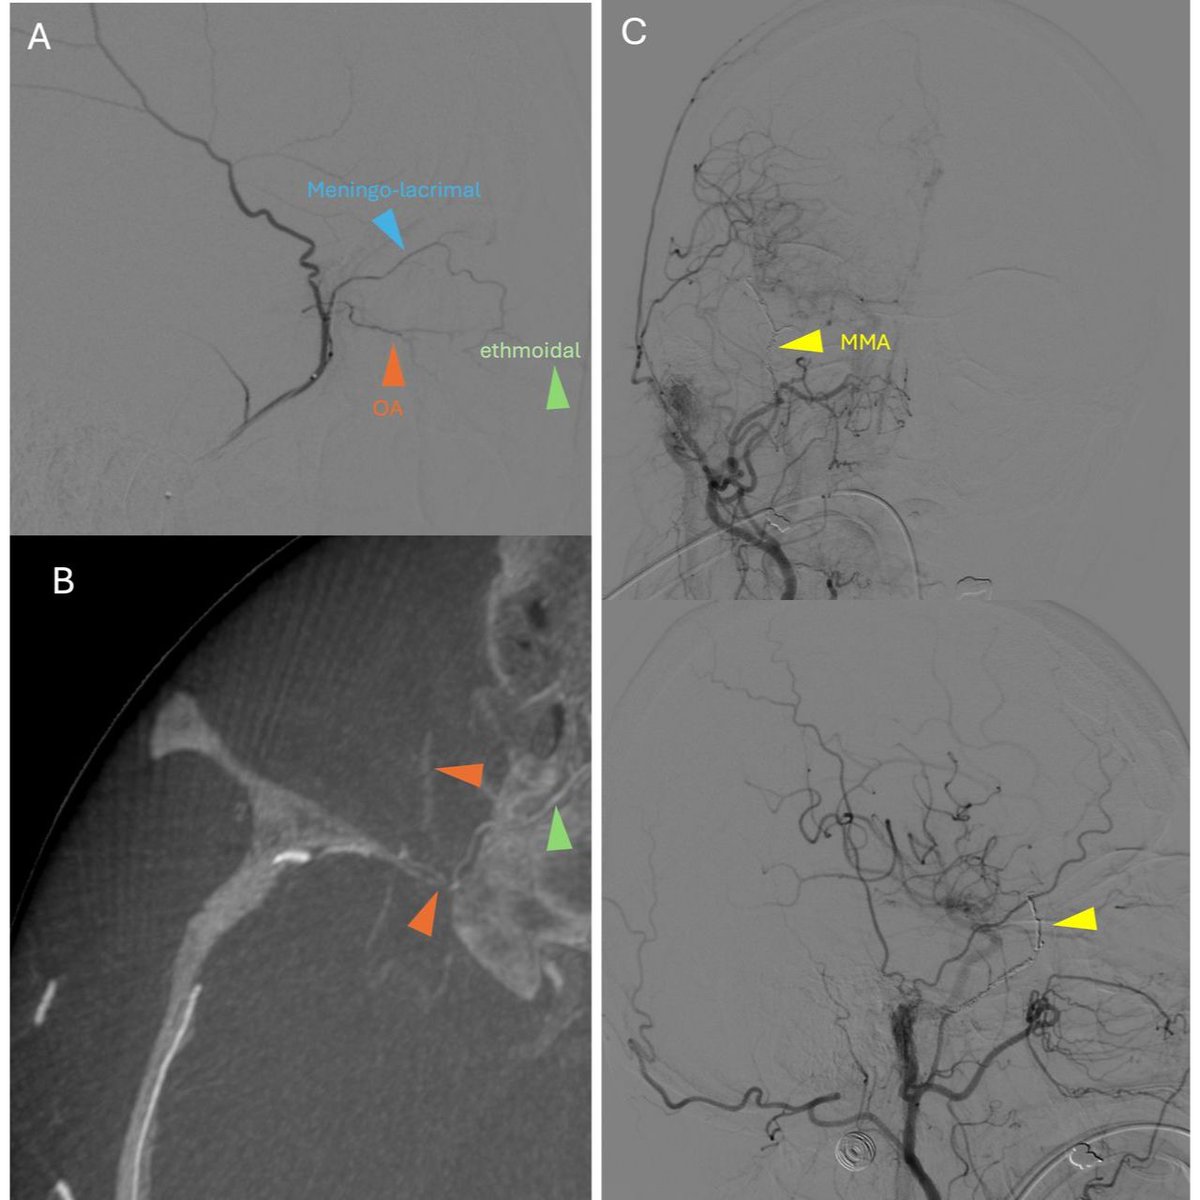

Ongoing controversy: Coils vs. other methods of MMA embolization for cSDH, which one is more safe and effective? Fecker et al. provide a retrospective review of 168 patients, 52% of whom were treated with coils and the balance with liquid embolics/particles. In their follow-up,

1

19

60